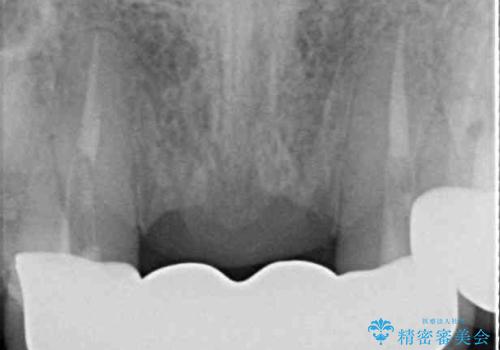

- 矯正治療を行った歯科医院で装着した前歯の仮歯が不快とのことで来院された患者様です。

仮歯自体はとても綺麗でしたが、2本の歯が欠損している部分に上唇小帯が入り込んでいたため、歯肉形成を行った上で仮歯を調整し、オールセラミックブリッジを装着することとしました。

上唇小帯を切除したことで、ブリッジのダミー部分に触れて腫れていた歯肉は健全な状態になりました。